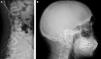

In the last six months, 17 people with terminal chronic kidney disease (CKD) on haemodialysis (HD) have come to the Hospital 12 Octubre Accident and Emergency Department to continue with their regular sessions. In recent years, the number of people arriving has continued to increase (Fig. 1). Each of these individuals reminds us that humanity and globalisation are failing, and that there is a gap in equity in access to RRT between countries. They are also teaching us the classic clinical signs of kidney disease, which Western nephrologists have forgotten, as they are the result of sustained underdialysis (Fig. 2). These people, after falling into debt to pay for treatment in countries where health coverage does not protect them, escape from their reality to continue living. Some of them, if they are lucky, have family or friends who take them in; others come alone and end up homeless. Migrants on RRT lack residence permits and work permits, in addition to suffering the employment problems of terminally ill patients who require hospital care three times a week.